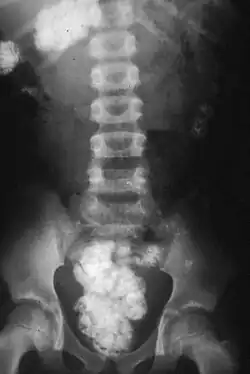

There are obvious health risks in the consumption of soil that is contaminated by animal or human feces; in particular, helminth eggs, such as Ascaris, which can stay viable in the soil for years, can lead to helminth infections.[43][44] Tetanus poses a further risk.[43] Lead poisoning is also associated with soil ingestion,[45] as well as health risks associated with zinc exposure can be problematic among people who eat soils on a regular basis.[32] Gestational geophagia (geophagia in pregnancy) has been associated with various homeostatic disruptions and oxidative damage in rats.[46]